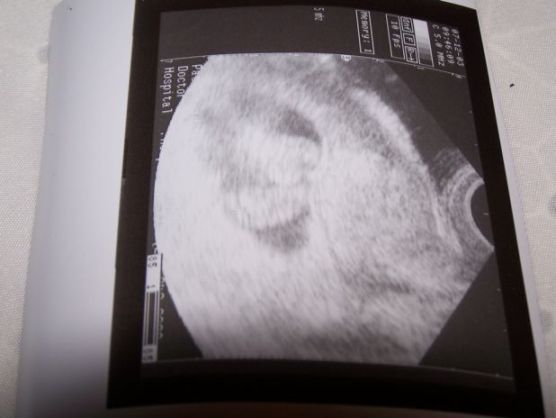

Nevettem magamon, nem is értettem, hogy gondolhattam azt, hogy netán terhes vagyok. Eltelt újabb két hét, még mindig nem jött meg. Vettem egy újabb tesztet, már direkt úgy kértem, hogy a legmegbízhatóbbat. A gyógyszertáros azt mondta, ez a teszt a legjobb, már 2 napos terhességet kimutat! Hát mondom, ha terhes vagyok, akkor már legalább 3 hetes, úgyhogy biztos kimutatja! Megint negatív lett. Mondom, hát ez nem igaz. Jártam a városban és még aznap vettem még egy, 3. fajta tesztet. Azon épphogy kivehető volt a második csík... mint utóbb kiderült, 5 hetes terhes voltam akkor.